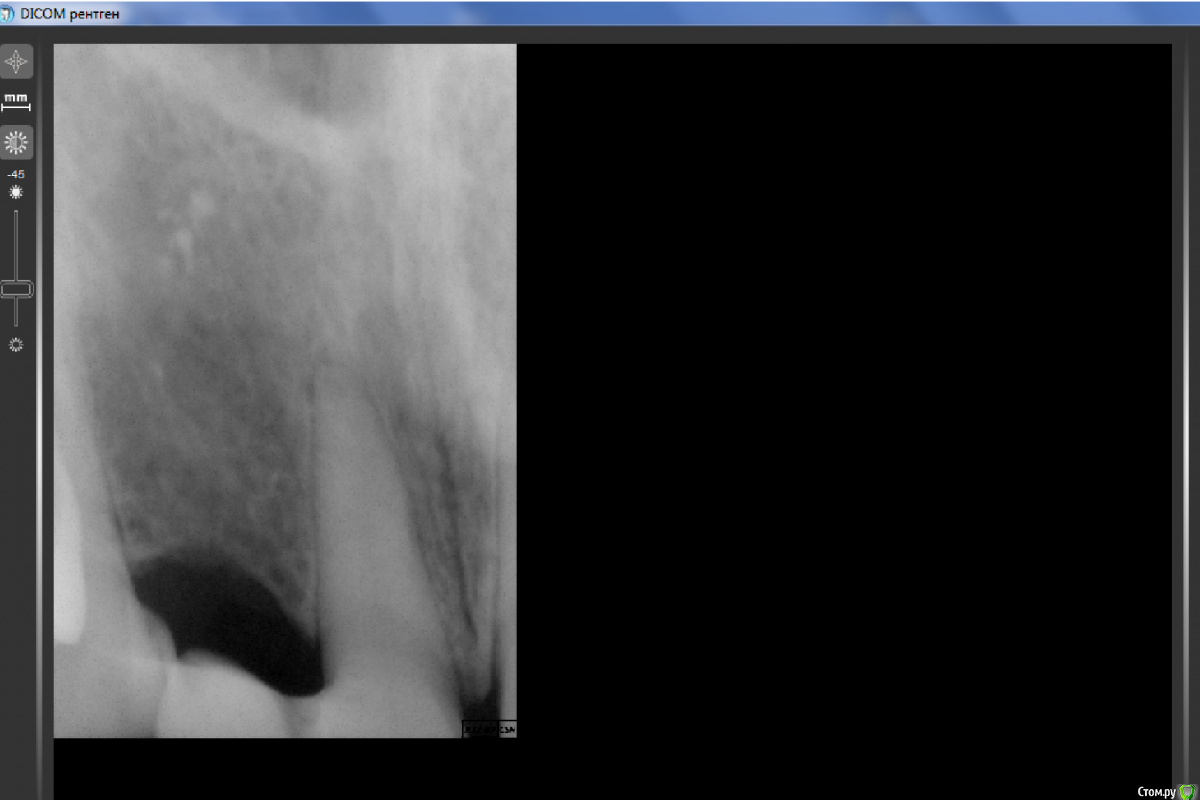

Evgen-Vozhd Опубликовано 12 мая, 2016 Поделиться Опубликовано 12 мая, 2016 (изменено) Пациентка после неудачной имплантации ходит около года с временным адгезивным мостом 13-11. Сегодня на приеме: жалобы на дискомфорт и побеление!!! 11 зуба. что это ?11зуб витальный, на прицельном снимке вроде всё спокойно Изменено 12 мая, 2016 пользователем Evgen-Vozhd Ссылка на комментарий

Evgen-Vozhd Опубликовано 13 мая, 2016 Автор Поделиться Опубликовано 13 мая, 2016 Что значит дискомфорт?Дайте снимок посмотретьНа счет побеления пациенты часто не всегда сразу что-либо замечают, возможно так было всегда? Или просто потемнел со временем 12 (енто же композит) и на его фоне 11 белее стал казаться. зуб белее по сравнению со своим "братом" 21-м. он тоже интактный Ссылка на комментарий